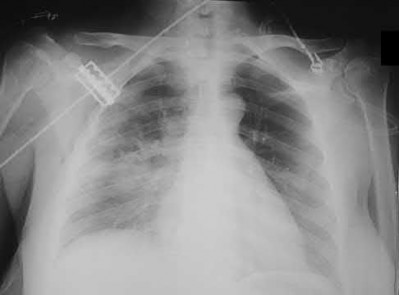

During head-on motor vehicle collisions occurring at highway speeds, airbag-protected individuals have a decreased rate (as compared to non-airbag protected individuals) of all of the following EXCEPT:

Corrent answer: 4

The referenced study by Loo et al. studied the interaction between airbags/seatbelts and mechanism of the crash (ie. front vs. side impact) and the injury patterns in these patients. They found that in frontal crashes, airbags reduced Glasgow Coma Scale severity in brain injury, facial fracture, shock, thoracoabdominal injuries and the need for extrication. Frontal airbags also had a protective effect on lower extremity fractures, but had no significant protective effect on pelvic fractures.